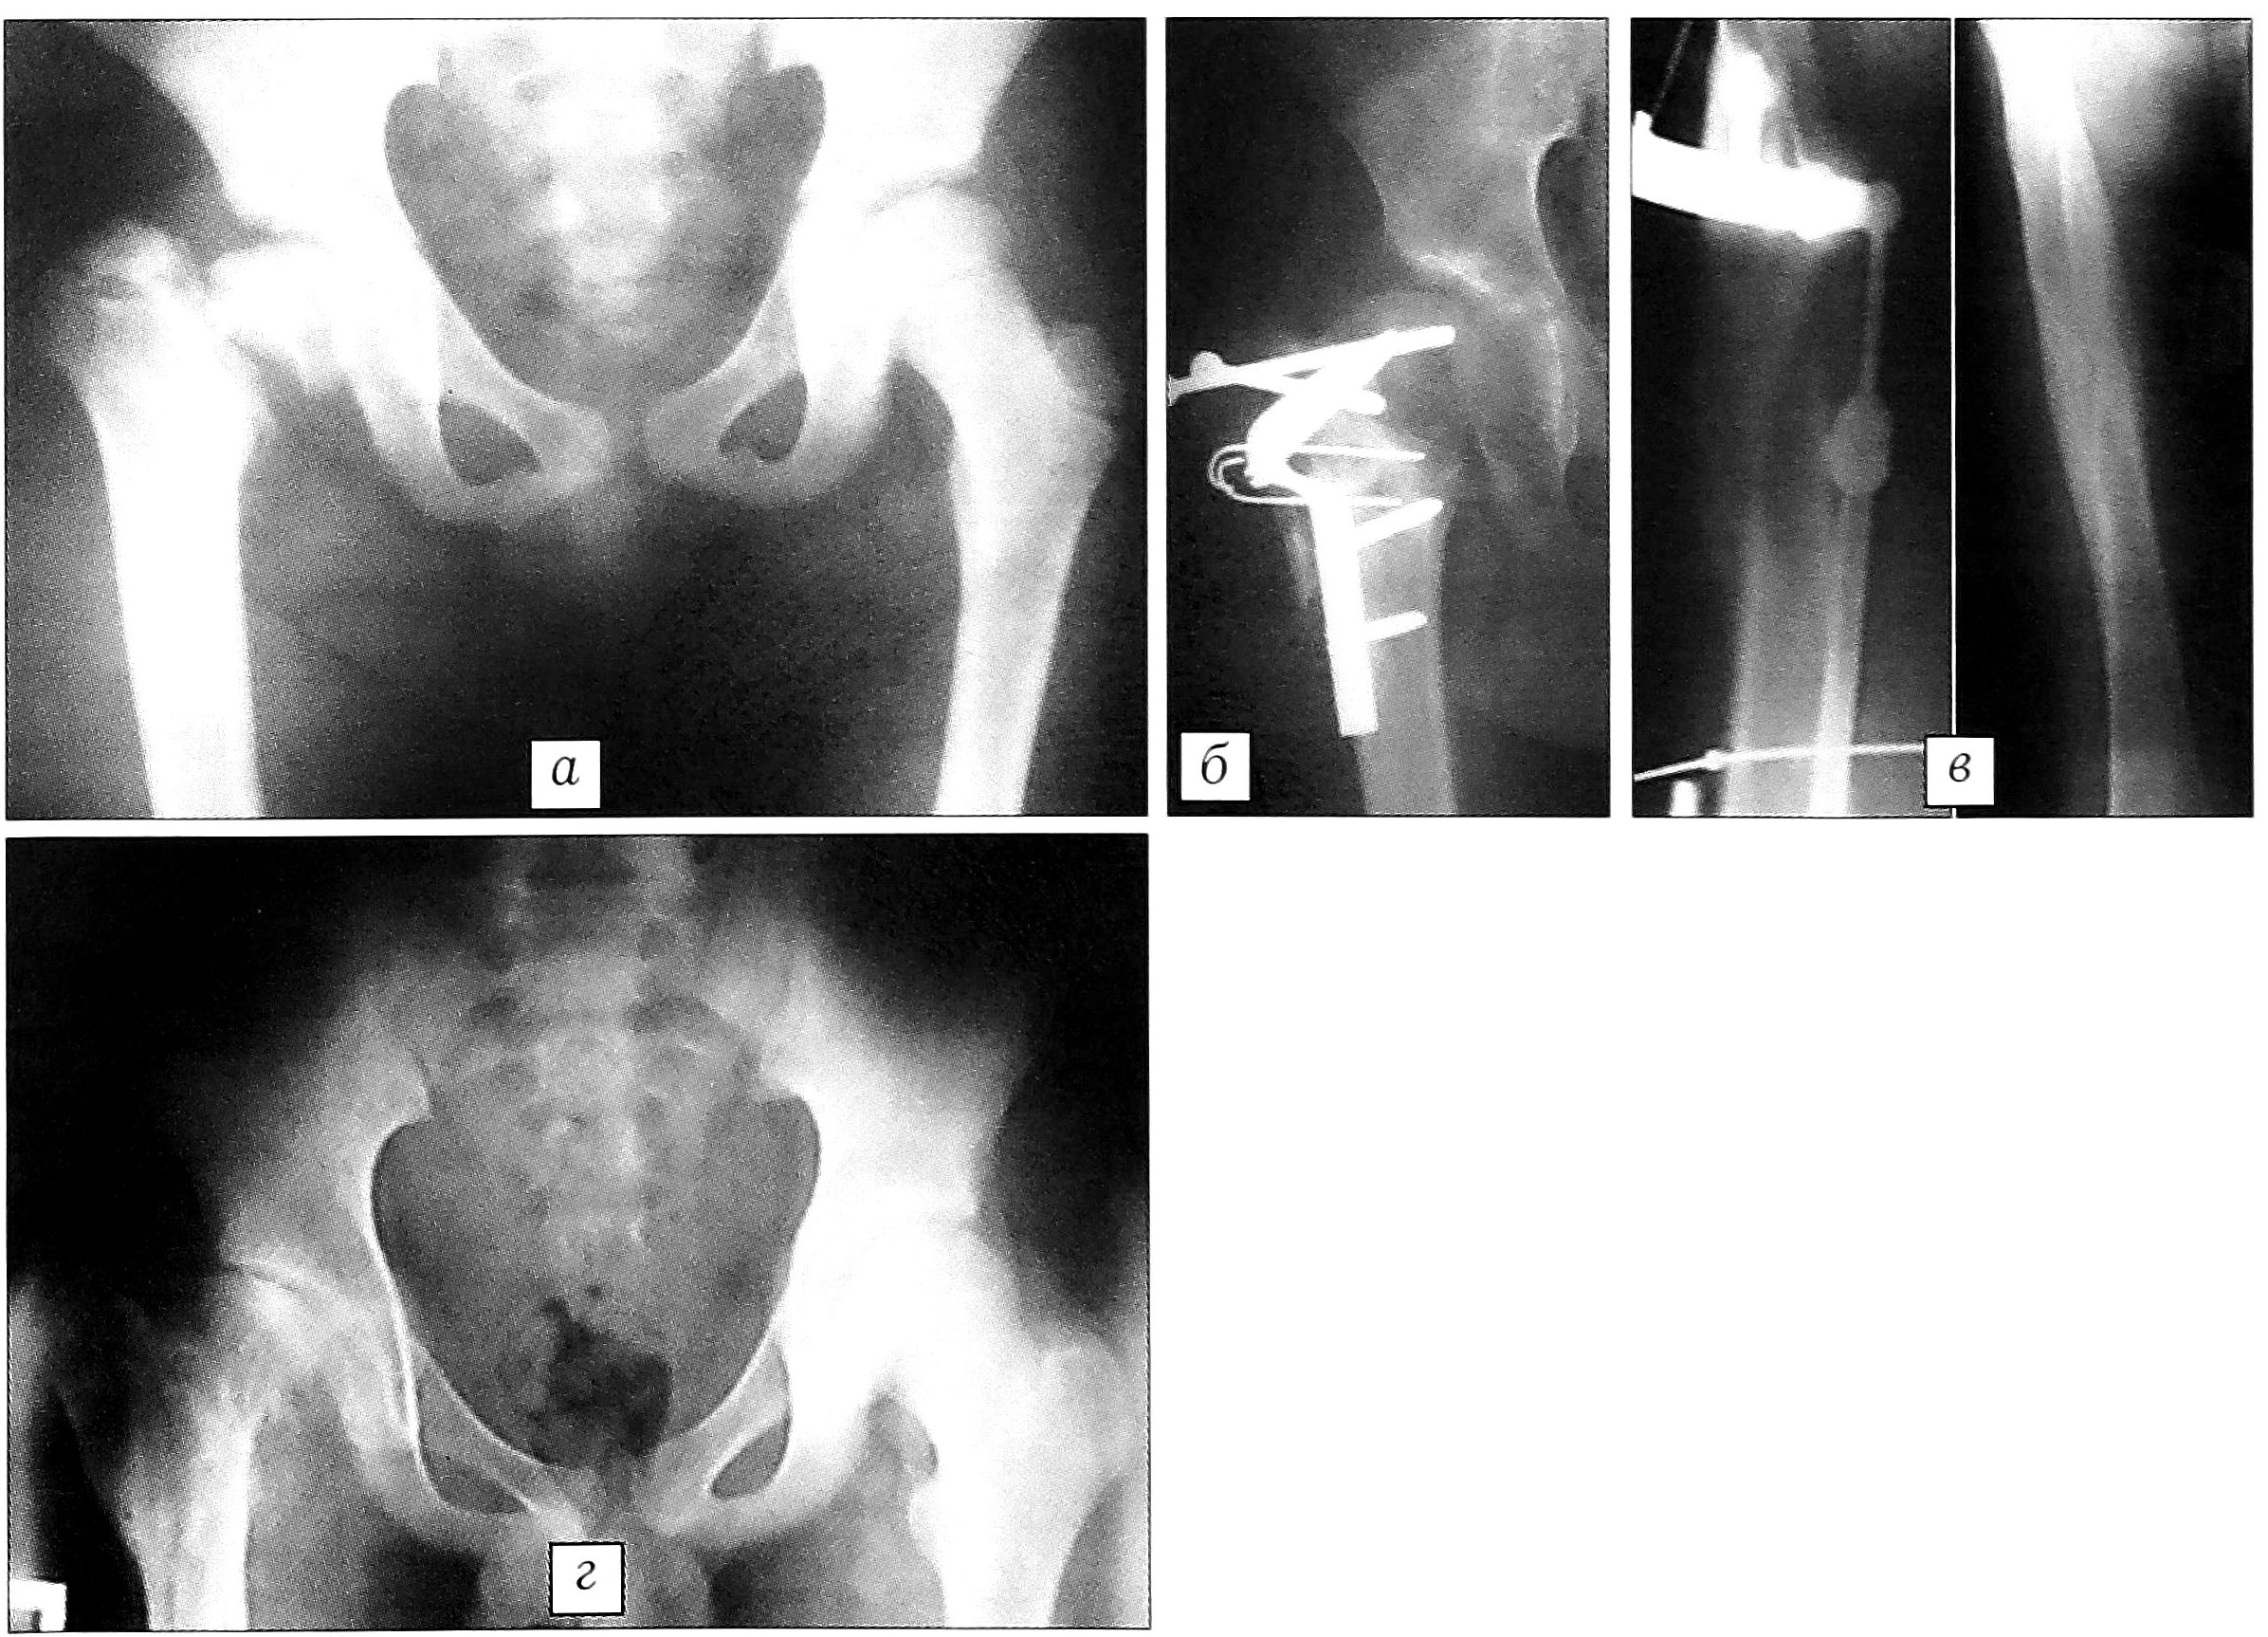

Больной П.,10 лет, диагноз: последствия гематогенного остеомиелита проксимального отдела правого бедра, остеолиз шейки с отделением головки от бедренной кости, варусная эпифизодиафизарная деформация правого бедра. Между головкой бедренной кости и вертельной частью прослеживается костный дефект размером около 2 см, шейка бедра отсутствует вследствие остеолиза (рис. 1, а). В верхней трети бедра имеются множественные рубцы, последние свищи закрылись около 6 лет назад. Хромота, положительный симптом Тренделенбурга, большой вертел правого бедра выстоит, выраженные нарушения функции ходьбы и опоры.

Оперирован 8.10.99. Фигурным доступом обнажен проксимальный отдела правого бедра. Выкроены два костных трансплантата: из большого вертела на проксимальной ножке из передней порции средней ягодичной мышцы и из метафиза бедра на дистальной ножке из латеральной порции четырехглавой мышцы. Иссечена межотломковая фиброзно-хрящевая ткань до обнажения костной медиальной поверхности большого вертела и торцовой части головки бедра. В образовавшийся дефект внедрены костно-мышечные трансплантаты, которые фиксированы двумя компрессирующими шурупами, двумя спицами и дополнительно швами за надкостницу. Резецирован по типу отщепа нижний полюс головки бедра, выполнена косая межвертельная остеотомия (снаружи—снизу кверху проксимально) с ориентацией на нижнюю часть головки, куда подведен и фиксирован дистальный фрагмент бедра с перекрытием зоны контакта большого вертела и головки (рис. 1, б).

Наступила консолидация головки бедра. Через 2 года после операции в связи с укорочением произведено удлинение этого же бедра на 8 см (рис. 1, в).

Больной осмотрен через 3 года после реконструкции проксимального отдела бедра. Ходит с полной нагрузкой на оперированную конечность. Отведение правого бедра до 50°, наружная ротация 30°, внутренняя — 20°. Симптом Тренделенбурга отрицательный. Болей нет. Длина конечностей одинакова. Коленный сустав полностью разработан. На рентгенограмме: структура головки бедра восстановлена, полное костное сращение, хорошая центрация головки в вертлужной впадине (рис. 1, г).

Рис. 1. Рентгенограммы больного П. 10 лет. а — исход хронического рецидивирующего остеомиелита: полный остеолиз шейки и частично головки бедра, головка лежит отдельно от смещенной кверху вертельной области; б — после реконструктивной операции по предложенному способу. Фиксация головки бедра и костно-мышечных трансплантатов винтами, спицами, пластиной типа Блаунта; в — в процессе и после удлинения бедра; г — через 3 года после реконструктивной операции: консолидация и восстановление структуры головки бедра, хорошая центрация в вертлужной впадине.